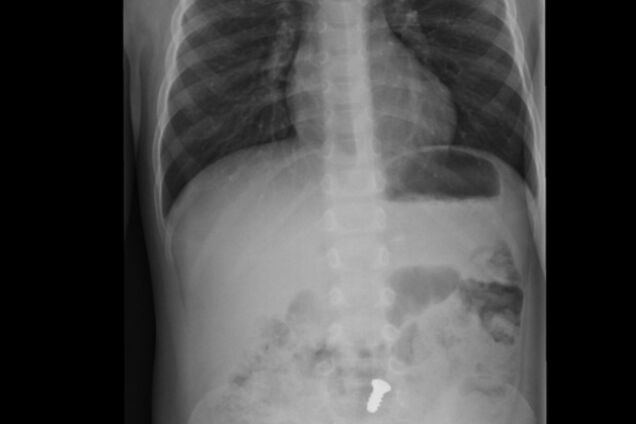

В знак протеста против решения администрации о его переводе в другую "зону" за пределами области, 36-летний мужчина, схлопотавший четыре года отсидки за грабеж, умудрился проглотить сразу два предмета – массивный болт и черенок от ложки более десяти сантиметров в длину.

Главный специалист областного управления Государственной пенитенциарной службы Елена Ковальчукговорит, что пожирателя металла взяли под наблюдение медики. Однако оперировать его для извлечения несъедобных изделий пока не планируют – надеются, что они выйдут из организма естественным путем.